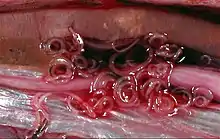

As with all parasites with a complex life cycle involving a number of hosts, details of the morphology vary depending on the host and life cycle stage. In the stage which infects fish, Anisakis species are found in a distinctive "watch-spring coil" shape. They are roughly 2 cm long when uncoiled. When in the final host, anisakids are longer, thicker, and more sturdy, to deal with the hazardous environment of a mammalian gut.

Within a few hours of ingestion, the parasitic worm tries to burrow though the intestinal wall, but since it cannot penetrate it, it gets stuck and dies. The presence of the parasite triggers an immune response; immune cells surround the worms, forming a ball-like structure that can block the digestive system, causing severe abdominal pain, malnutrition, and vomiting. Occasionally, the larvae are regurgitated. If the larvae pass into the bowel or large intestine, a severe eosinophilic granulomatous response may also occur one to two weeks following infection, causing symptoms mimicking Crohn's disease.[12][13]

Diagnosis can be made by gastroscopic examination, during which the 2-cm larvae are visually observed and removed, or by histopathologic examination of tissue removed at biopsy or during surgery.